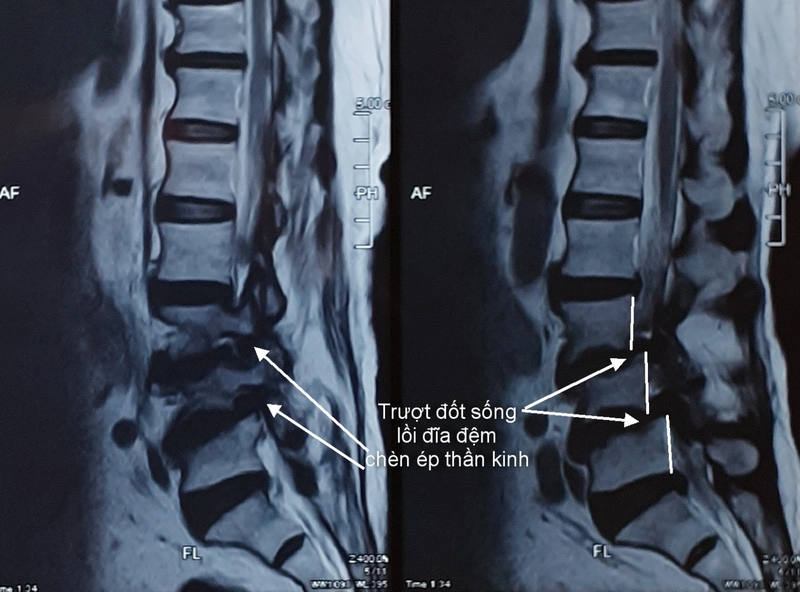

Chụp cắt lớp vi tính cột sống được sử dụng để chẩn đoán và đánh giá nhiều vấn đề liên quan đến cột sống, bao gồm gãy xương, thoái hóa đốt sống, thoát vị đĩa đệm, khối u và các bệnh lý khác. Thông tin từ các hình ảnh CT có thể giúp bác sĩ xác định chính xác tình trạng của bệnh nhân và lập kế hoạch điều trị phù hợp.